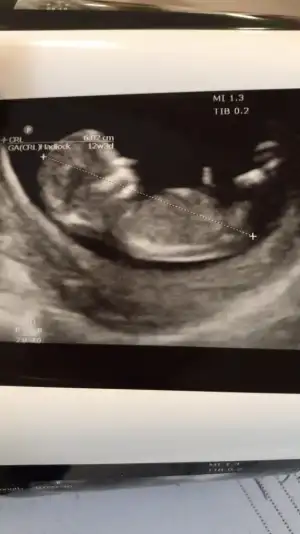

9 haftalık bizi de tahmin eder misiniz

Eklentiler